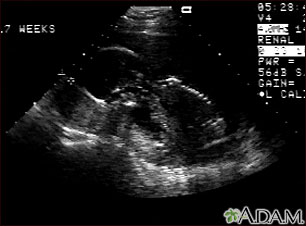

A pregnancy ultrasound is an imaging test that uses sound waves to create a picture of how a baby is developing in the womb (uterus). It is also used to check the female pelvic organs during pregnancy.

Some centers are now performing a pregnancy ultrasound called a nuchal translucency screening test around 9 to 13 weeks of pregnancy. This test is done to look for signs of Down syndrome or other problems in the developing baby. This test is often combined with blood tests to improve the accuracy of results.

Normal Results

The developing baby, placenta, amniotic fluid, and surrounding structures appear normal for the gestational age.